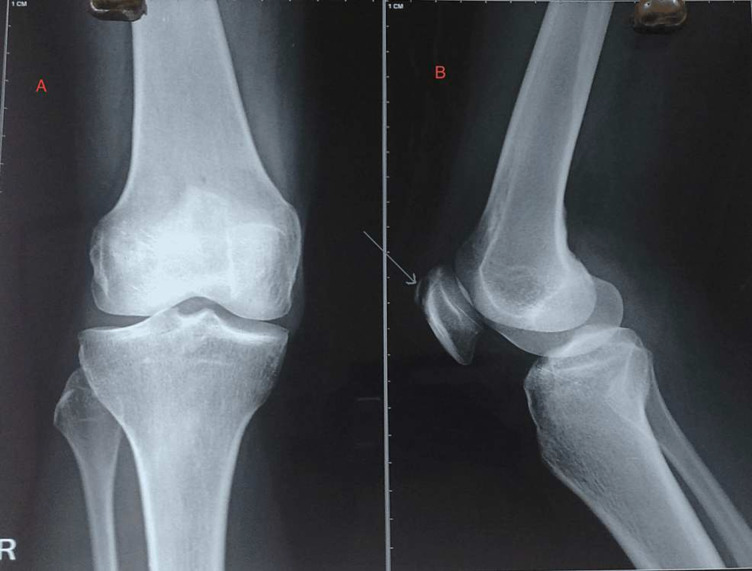

Radiographic imaging of the affected knee revealed a lytic lesion localised in the proximal pole of the patella, predominantly visible on lateral projection (figure 2). Notably, the articular margin of the patella remained intact, with no evidence of cortical breach. The possible differentials at this stage were tumorous conditions of the patella (giant cell tumour, aneurysmal bone cyst, etc), non-specific osteomyelitis and TB of the patella. Chest X-ray findings were unremarkable, ruling out pulmonary involvement. Sputum examination for acid-fast bacilli (AFB) yielded negative results, and limitations of sputum examination include its variable sensitivity, particularly in extrapulmonary TB, where bacillary load may be low. False-negative results can occur due to inadequate sample collection, intermittent shedding of bacilli or the presence of non-acid-fast mycobacteria. A needle biopsy was done from the affected site (proximal pole of patella) under fluoroscopic control. Histopathological examination of the tissue obtained via needle biopsy revealed epithelial cell granulomas with central caseous necrosis, indicative of TB, along with the presence of Langerhans-type giant cells, suggestive of TB. Despite negative Ziehl–Neelsen staining for AFB, PCR testing confirmed the presence of Mycobacterium tuberculosis DNA, solidifying the diagnosis of TB. Due to financial constraints, MRI of the knee could not be obtained.

Figure 2. Anteroposterior (A) and lateral projection (B) of X-ray of the right knee. The anteroposterior view (A) seems innocuous, while the lateral projection (B) shows a lytic lesion over the proximal pole of the patella (arrow).